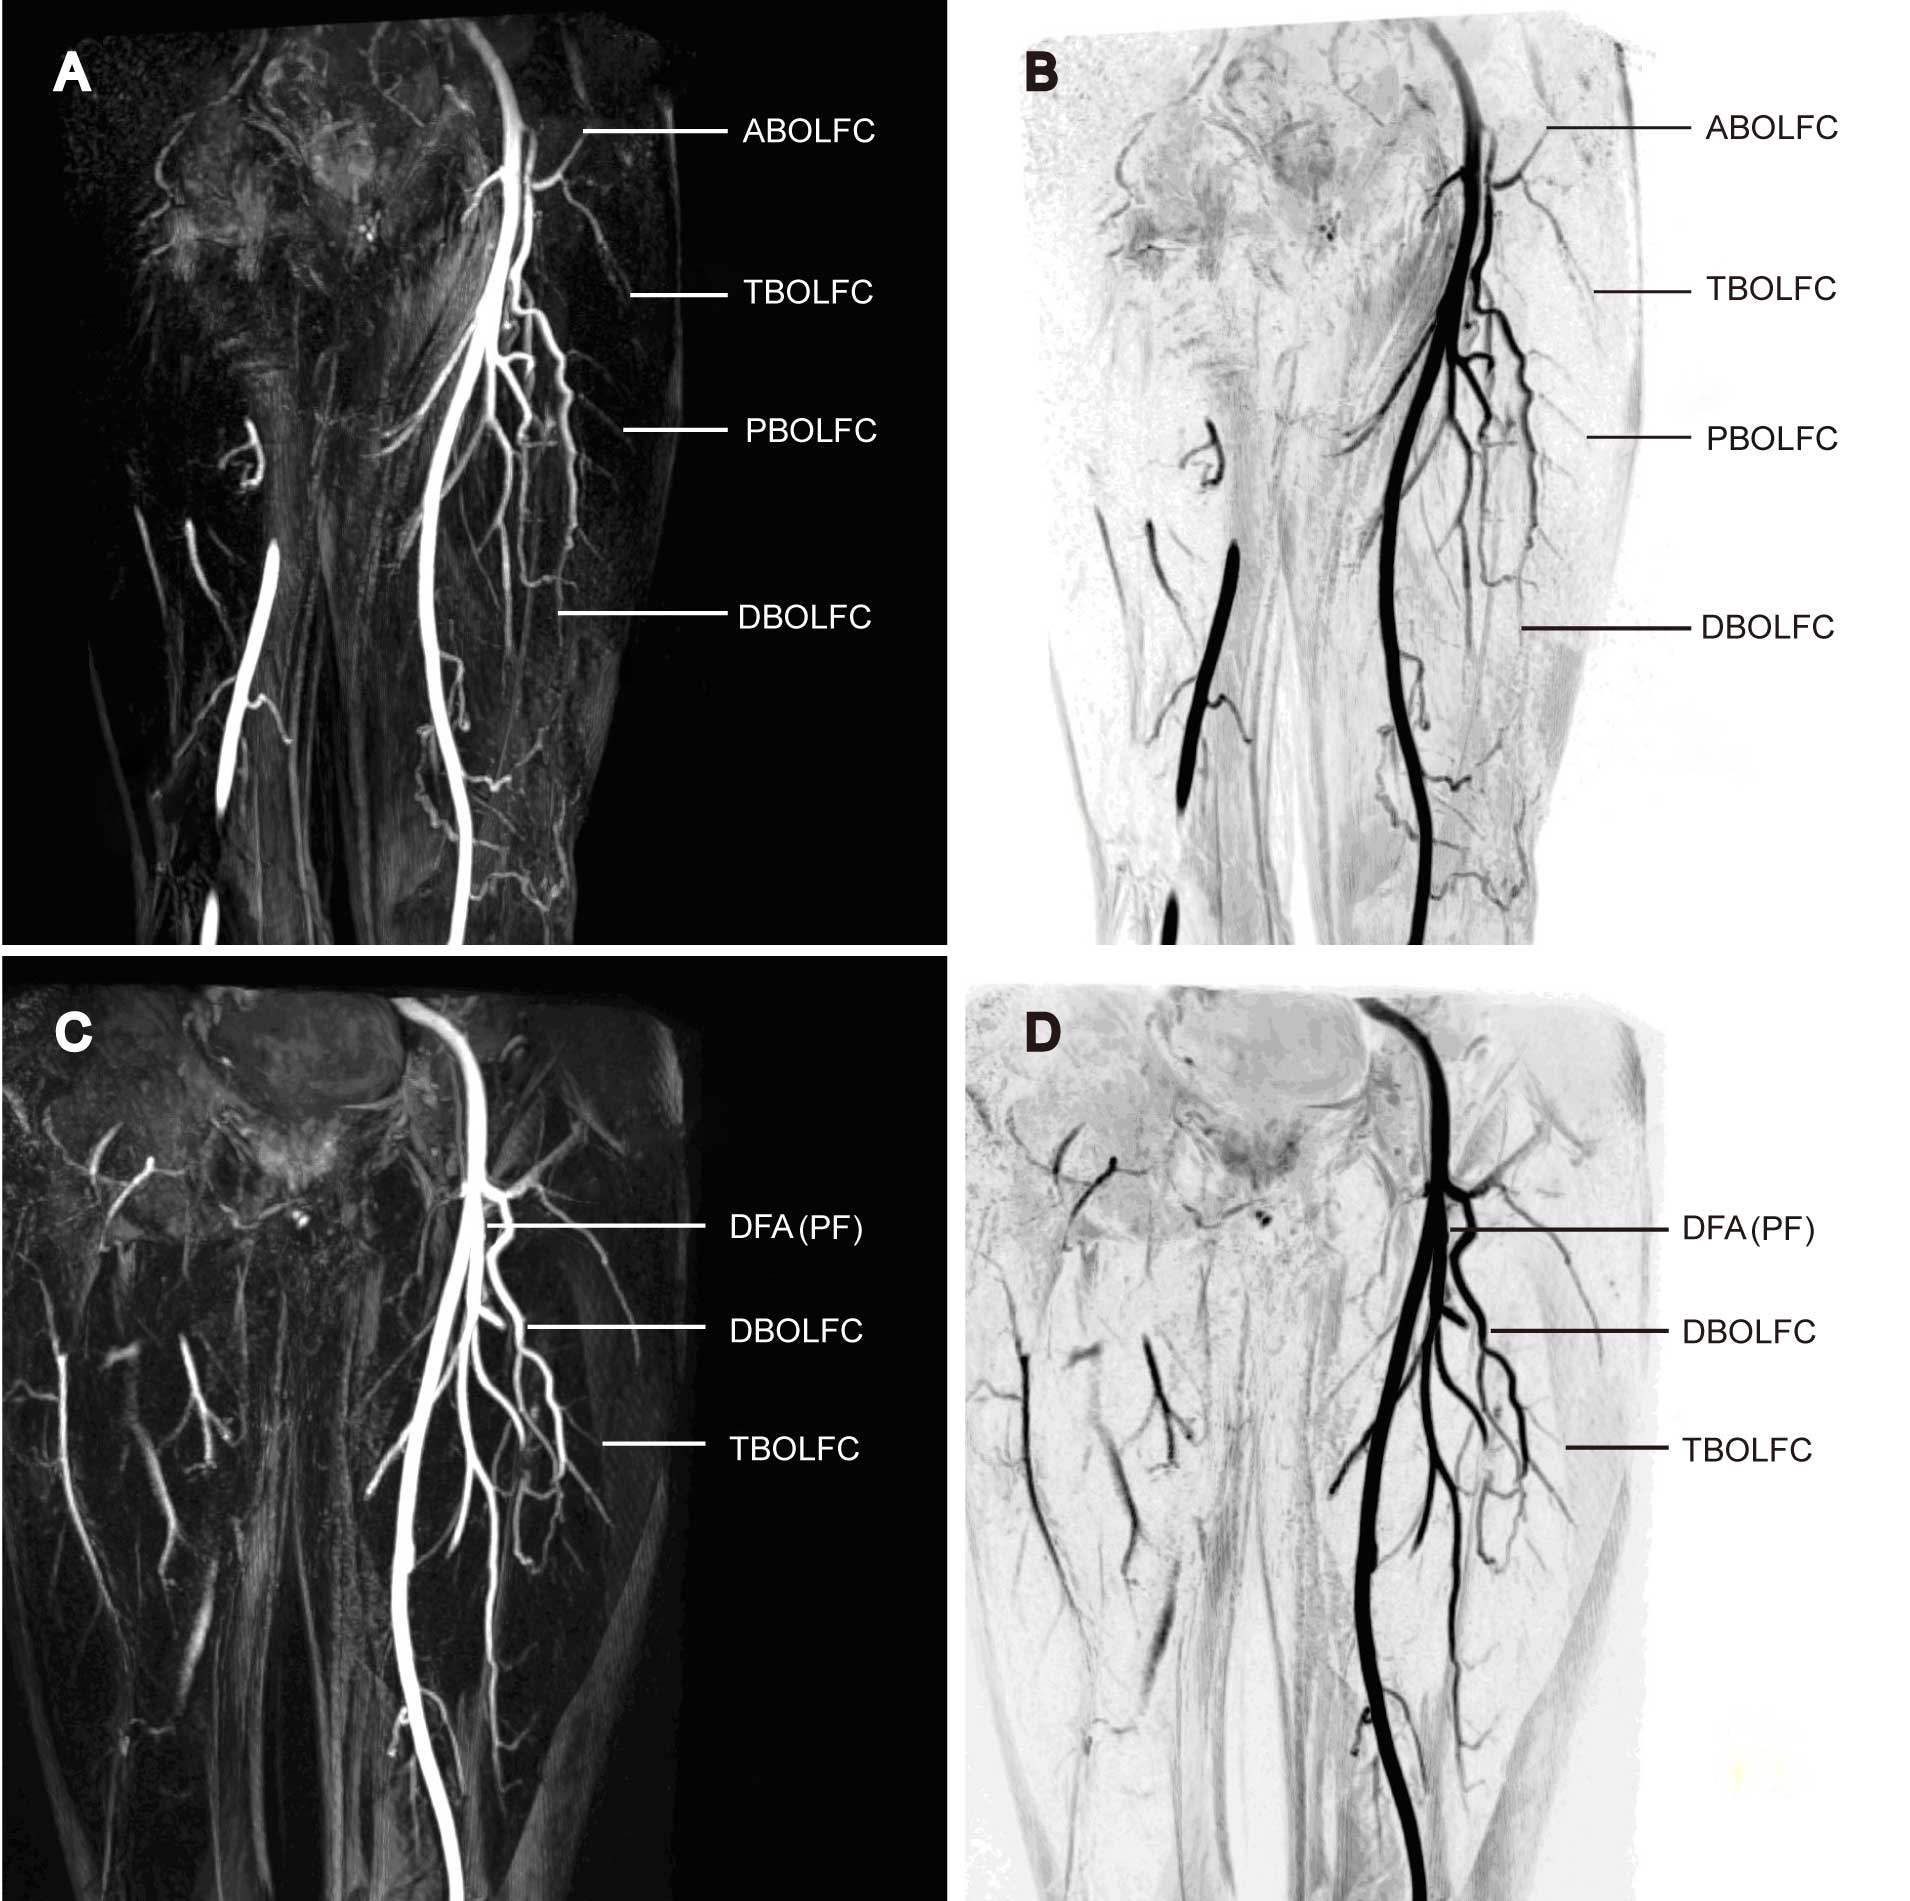

LFCA perforating branches and flap outline

All three-tier LFCA branches were well visualized in subtractive 3D-MRA. Thick-slab MIP revealed the distribution and spatial pattern of the vessels, and TS-MIP ignored unrelated data to better visualize the target anatomy, namely the LFCA and its secondary and tertiary branches (Fig. 4A and B). The descending branch of the right LFCA was found to trifurcate into three parallel perforating arteries (Fig. 5A and B). The space between the terminal perforating arteries and the skin was clearly visualized to help in the decision of the surgical approach and the evaluation of flap outlining. The proposed flap was therefore primarily supplied by the LFCA descending branch. By contrast, the left LFCA descending branch extended into a single artery, without visible perforating arteries (Fig. 5C and D). The LFCA transverse branch was shown to be proximal to the skin, and its caliber could be precisely evaluated using MRA. For each patient, flap size was adjusted based on the surface area of limb cutaneous and subcutaneous tissue defects. According to the preoperative MRA results, the flaps were designed to encompass the center of the blood vessel (perforating artery pedicle), and typically 5–8 cm diameter flaps were appropriate.

Figure 4.

(A) Contrast-enhanced magnetic resonance angiography three-dimensional reconstructed maximum intensity projection and (B) digital subtraction angiography showed that the LFCA originated from the anterolateral part of the DFA. The pathways of the descending branch, the DFA and the superior genicular artery were well visualized. The perforating arteries arose from the transverse branch, and the space between the terminal perforating artery and the skin was also well visualized. LFCA, lateral femoral circumflex artery; ABOLFC, ascending branch of the LFCA; TBOLFC, transverse branch of the LFCA; tblofc, perforating branch of the LFCA; DBOLFC, descending branch of the LFCA; DFA (PF) 3rd PA, the third peripheral branch of the deep femoral artery (profunda femoris).

Figure 5.

(A and C) Contrast-enhanced magnetic resonance angiography two-dimensional reconstructed thin-slab maximum intensity projection and (B and D) digital subtraction angiography images showing the LFCA and its branches. LFCA, lateral femoral circumflex artery; ABOLFC, ascending branch of the LFCA; TBOLFC, transverse branch of the LFCA; PBOLFC, perforating arteries of the LFCA; DBOLFC, descending branch of the LFCA; DFA (PF), deep femoral artery (profunda femoris).